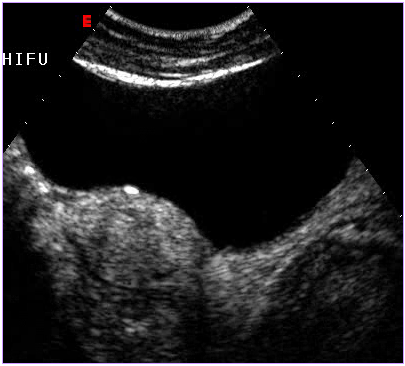

治療后壞死的子宮肌瘤不會(huì)消失,而是會(huì)發(fā)生纖維化,緩慢縮小,但對(duì)人體已經(jīng)沒(méi)有危害了。最近,由于磁共振增強(qiáng)掃描(圖1,2)和超聲造影檢查技術(shù)(圖3,4)的應(yīng)用,使治療效果的評(píng)價(jià)更加客觀和明確。

圖3 治療前超聲造影